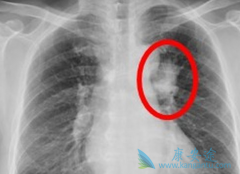

常见的肺癌放疗的副作用有哪些?如何处理?

放射治疗是目前临床上肺癌治疗的常用方法之一,肺癌放疗是使用许多精确的辐射光束集中在一个很小的病灶部位进行照射,以达到杀死癌细胞的效果。虽然肺癌放疗过程是无痛的,但是却会给患者带来很多副作用。 肺癌放疗的副作用 有哪些,该如何处理这些副作 ...